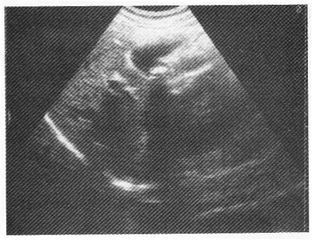

女性,30岁,反复右上腹疼痛2年余,反射至肩背部疼痛;超声检查如图所示。

6.根据超声图像诊断为

C.胆囊结石

正确答案:6.C;7.C;8.E解题思路:1.该例临床症状无特异性,超声图像是典型的结石表现。

2.胆囊结石与胆囊息肉超声鉴别最主要点是:结石随体位改变而移动,胆囊息肉生长在胆囊壁上不随体位改变而移动。

3.胆囊肿瘤可因表面有钙盐沉积而表现为强回声,但多不伴声影,重要的是不随体位改变而移动;结石随体位改变而移动。